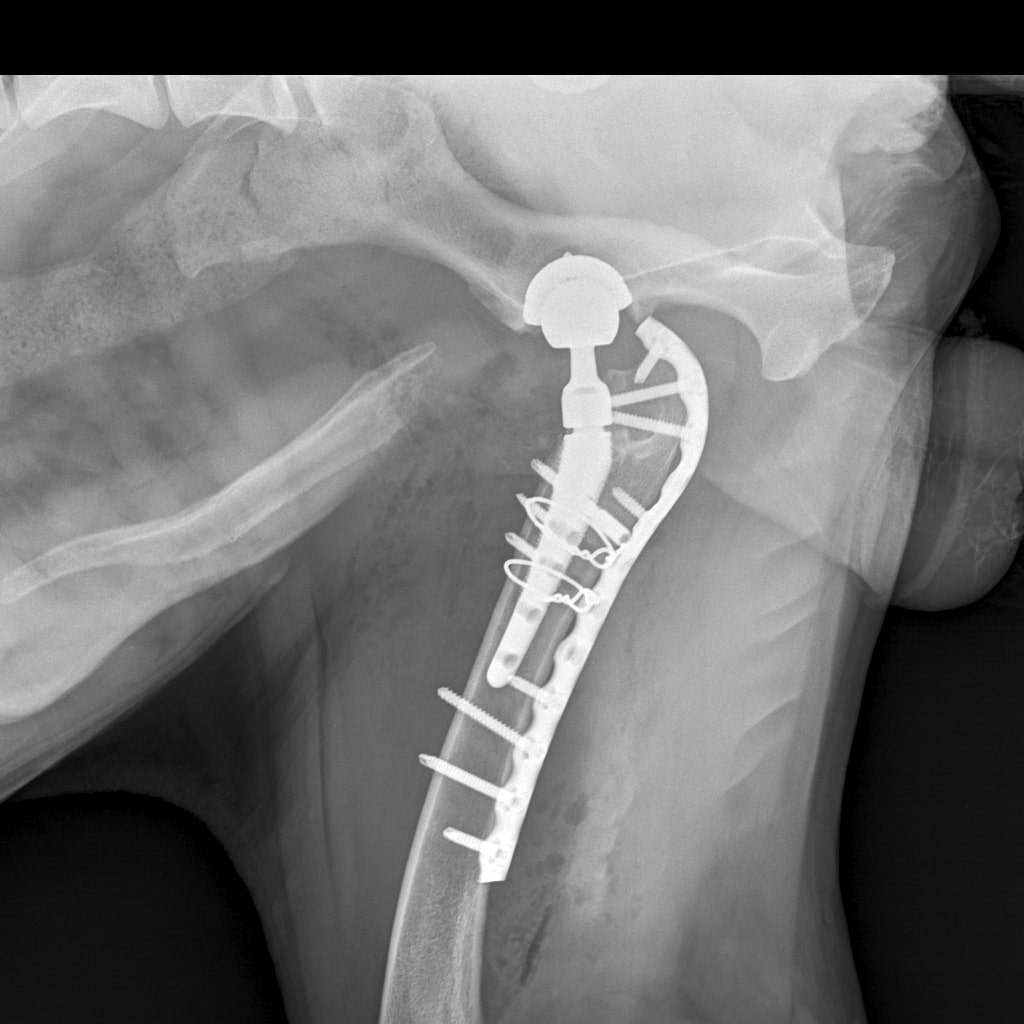

F37B4905-A77F-43B7-A3A7-4AAD9E739F82.jpeg

E6A744CC-768F-480D-8917-7FDAD53F05BD.jpeg

DA1A1524-BA63-434B-95BE-C121F7D5334F.jpeg

4D4A6426-4FE5-4417-ACCB-6DE53B57B90E.jpeg

E358D56E-67BF-4D4C-B3F0-BF8F4089D7A2.jpeg

767DD36C-E2E2-41FB-9CCF-6940421D2BB2.jpeg

701487DA-D6D9-4CE0-B18B-EEB120E78EF2.jpeg

Мы ничего не оплачивали. Все включено.

За время противовоспалительной терапии снизилось воспаление и в левом тазобедренном суставе, но увы, форма головки бедренной кости и состояние шейки бедра , лучше не стали:(((

Операция однозначно нужна.

Снимки столь качественные, что их можно в учебник